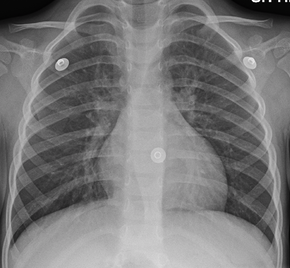

Bronchitis affects roughly 8.6 million people in the US alone. There are 2 types of Bronchitis and each one is deadly in its own right. It is an acute lung disease that causes a build up of mucus in the lungs. It kills about 457 per every 100,000 people which is roughly .5% of the population. In this article, the details of the two most common types of bronchitis will be covered.

Acute Bronchitis, otherwise known as a chest cold, happens when the airways of the lungs expand and produce mucus. This causes a disturbance in breathing and leads to fits of coughing and asthma. It is temporary and lasts for about 3 weeks. A viral infection is commonly one of the causes of acute bronchitis. Most of the time, they are the same viruses that cause colds and the flu. It can also be caused by inhaling small particles that irritate the respiratory system. Dusts, allergies, and powerful fumes, like cigarette smoke and factory fumes, are examples of these. Acute bronchitis can also happen to individuals who have chronic sinusitis, allergies, or swollen tonsils and adenoids. It can be fatal in persons who have lung or heart illness. Pneumonia is another type of side effect that could be fatal. Acute bronchitis is usually treated within the body without any sort of medical intervention needed. Some shots can be taken to lessen symptoms and to prevent it from happening again.

Chronic bronchitis is long-term inflammation of the bronchi, which are the airways of the lung. It is common among smokers or other people who have used vapes, etc. People with chronic bronchitis have weaker lungs and their lungs get infected much easier compared to the lungs of a healthy individual. Sometimes, they have periods of acute bronchitis where their symptoms get much worse than normal. Chronic bronchitis is described as having a cough for at least a quarter of the year for 2 years in a row. Chronic Bronchitis, unlike Acute Bronchitis, isn't caused by a virus or bacteria. It is instead caused by smoking with air pollution and the environment playing a significant factor as well. It can be treated by quitting smoking and staying away from smoke in general.

In conclusion, Bronchitis is a lung disease which leads to congested airways and patients have trouble breathing. Bronchitis leads to a buildup of mucus in the lungs and can lead to coughing with or without phlegm. The number of cases of bronchitis has increased over the course of the decade and it is speculated to increase even further. One of the main reasons for this is due to the increasing pollution and chain smokers.